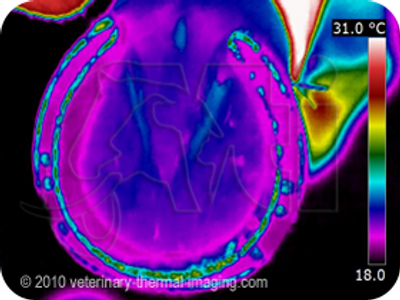

Notice pic on left, the image shows the color black where the horse bares more weight versus the purple area of the shoe shows the horse bearing less weight. It should be symmetrical in weight displacement on the shoe and the color of the shoe on our image should be the same .

Look at these thermal images for out of balanced feet.

Image on the right: the color black on the right side of the shoe is where the horse bares more weight, causing a imbalance. Within a few minutes of lounging the thermal image was taken.